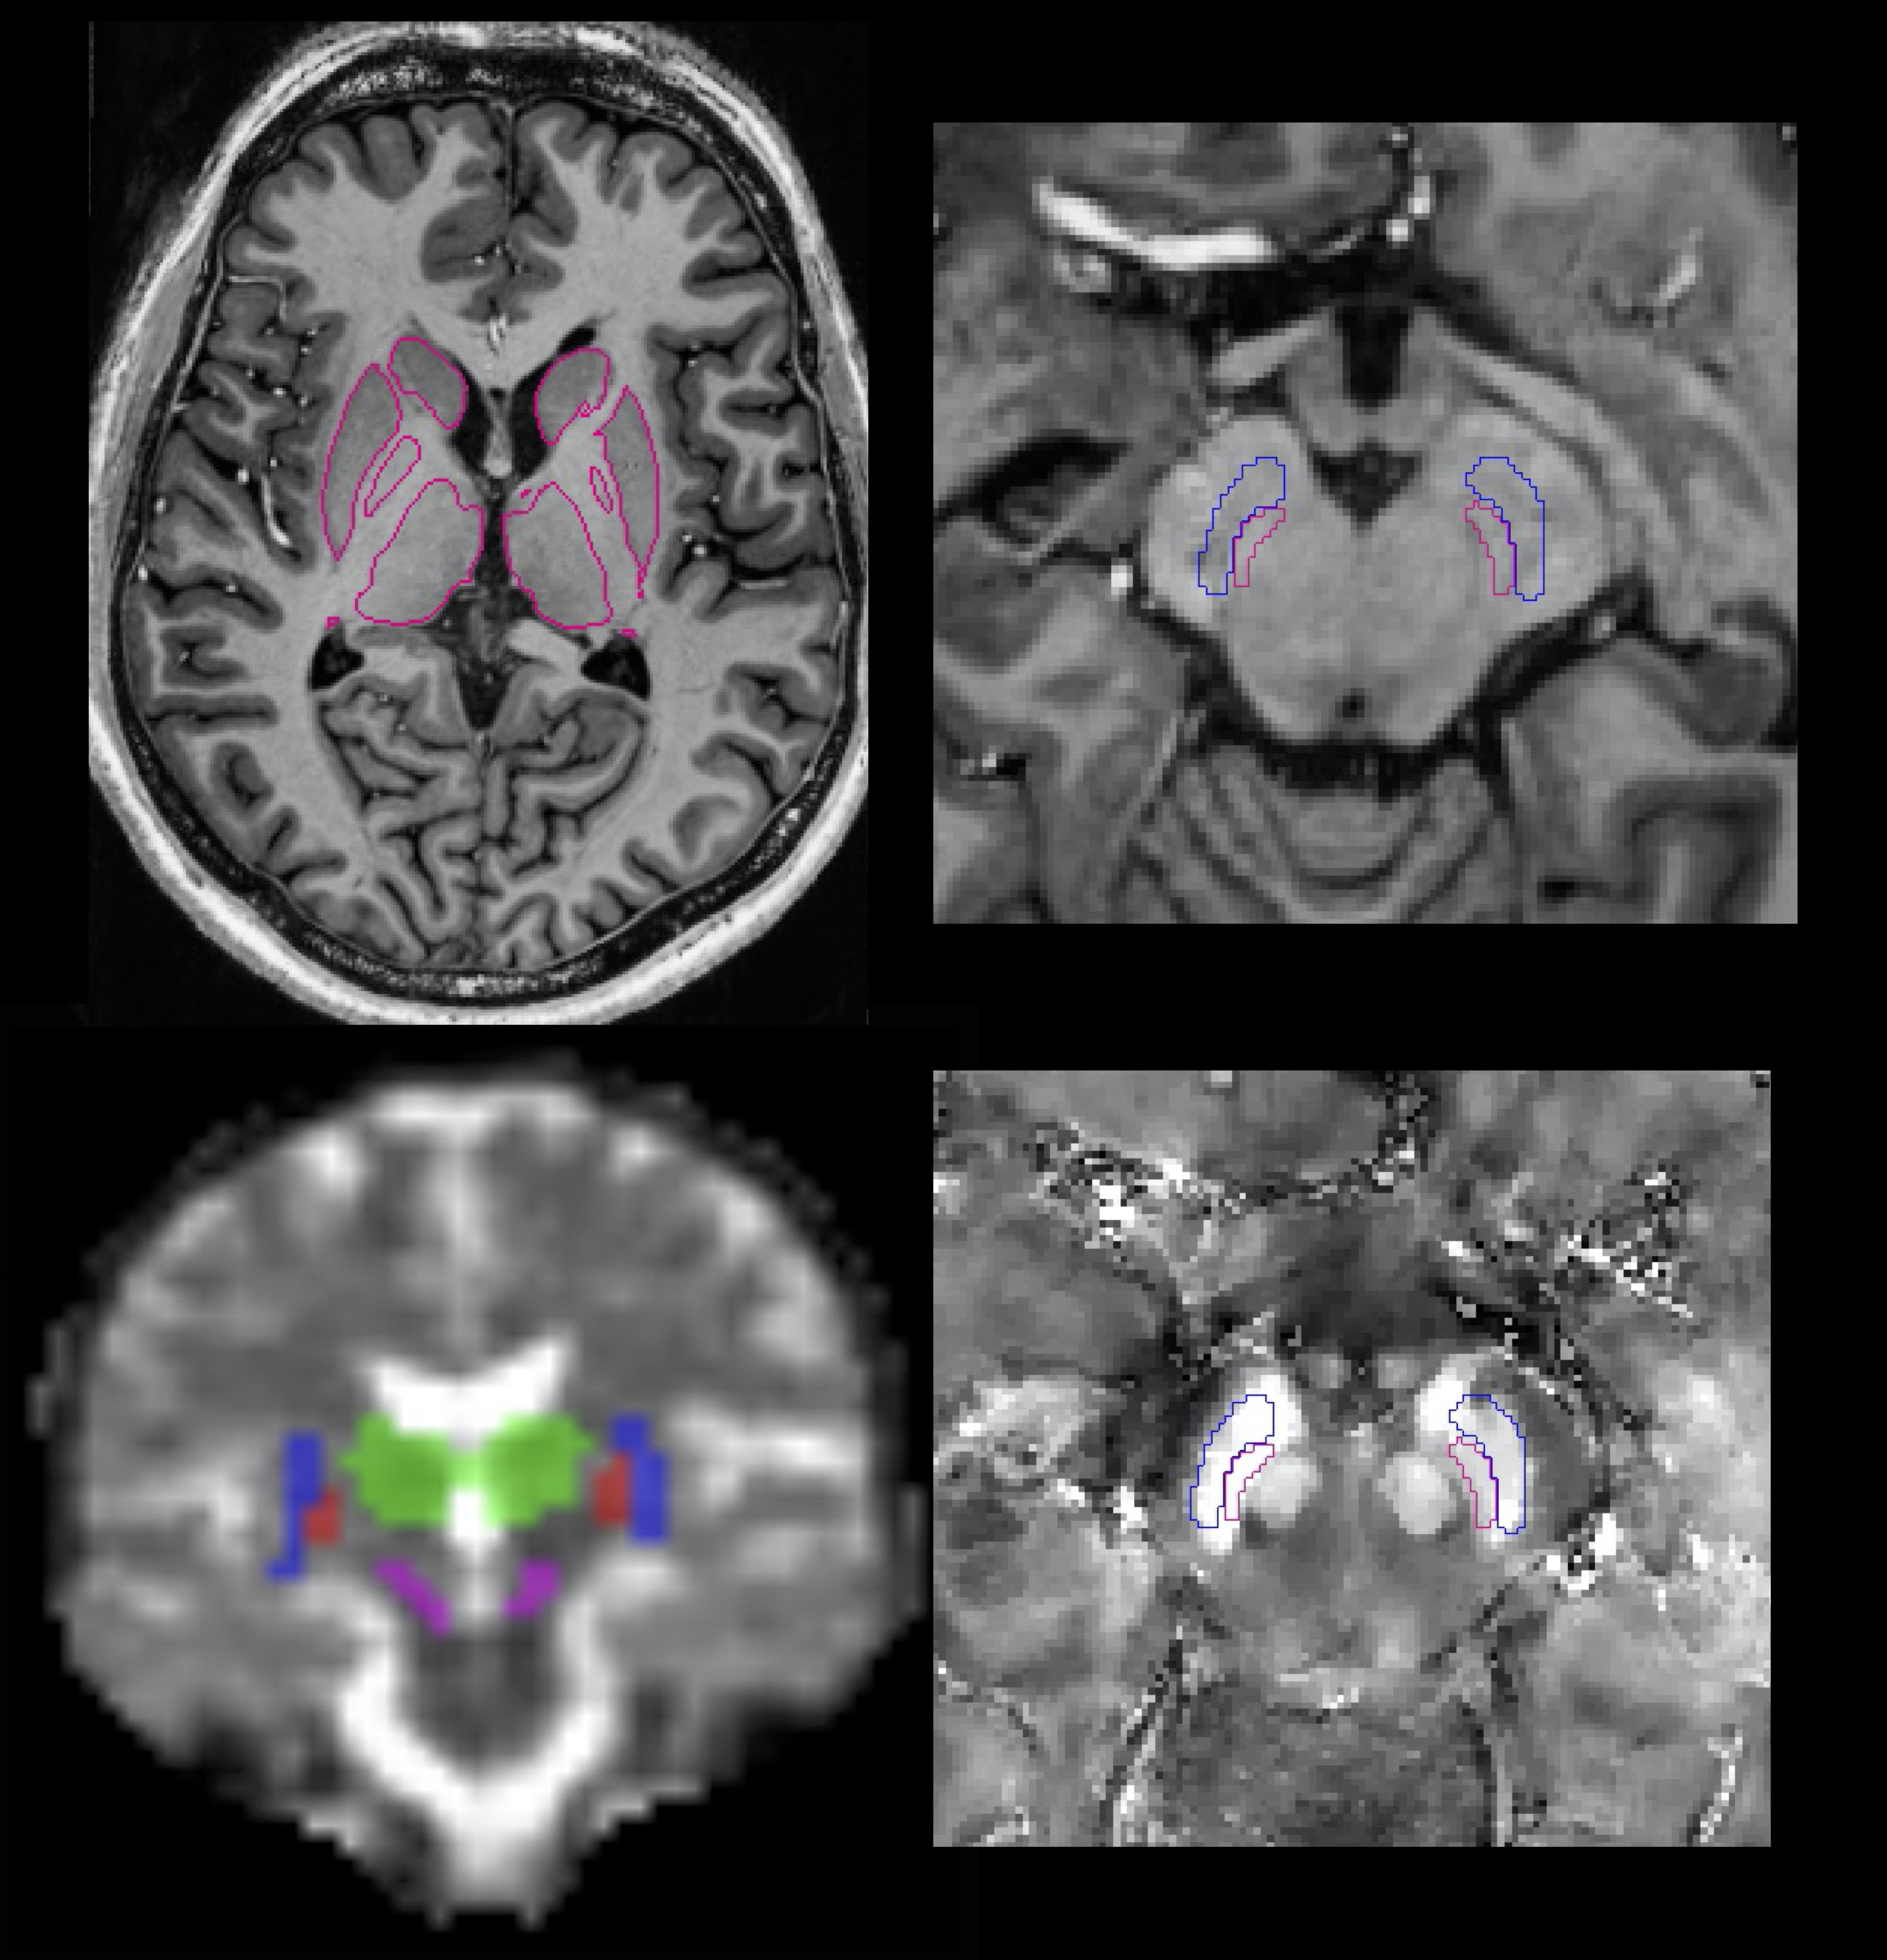

The group conducts MRI clinical research using advanced MR biomarkers (@ 3T & 7T) developed in the team to better understand and predict the mechanisms and consequences of the pathophysiological processes occurring in Multiple Sclerosis, Epilepsy, ALS, Spinal cord injury and other diseases such as Parkinson, AD, myelopathies, anorexia and obesity. Concurrently, function and dysfunction of specific neural networks (visual, attentional systems) are studied using these pathologies as models.

- Inhomogenous Magnetization Transfer (ihMT)

- New MR Biomarkers

- Quantitative MRI

- Sodium MRI